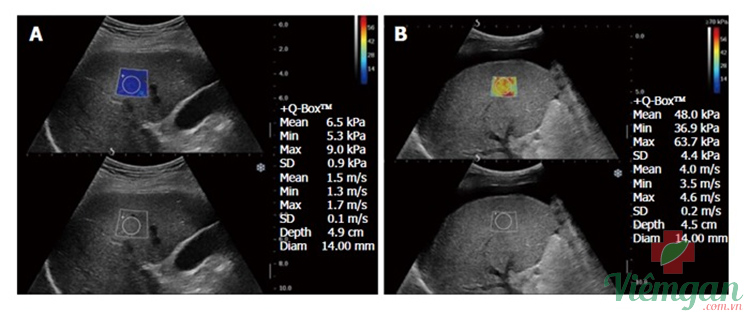

Hình ảnh 3

Trong hình ảnh siêu âm, vùng quan tâm nằm ở phần thùy phải của gan khi quét theo hướng liên sườn. Bên phải màn hình hiển thị tốc độ sóng biến dạng, được đo bằng kPa và m/s. Các màu sắc biểu thị sự biến dạng thời gian thực của các điểm ảnh, phản ánh độ đàn hồi của chúng trong hình ảnh chế độ B tiêu chuẩn.

- Màn hình A: Giá trị tốc độ sóng biến dạng bình thường

- Màn hình B: Siêu âm thấy tốc độ sóng biến dạng tương ứng với bệnh xơ gan. Màn hình cũng cho thấy sự xuất hiện của lượng lớn dịch cổ trướng.